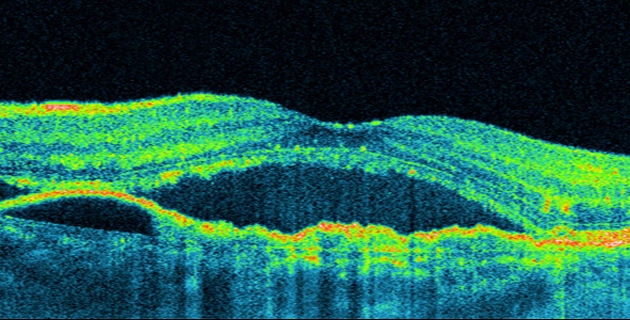

Im Gegensatz zur trockenen (atrophen) Form, die meist nur langsam und schleichend voranschreitet und für die es keine kausale Heilungsmöglichkeit gibt, handelt es sich bei der feuchten (exsudativen) Makuladegeneration um eine Form, die schnell zur Leseblindheit führt. Mittels Fluoreszenzangiographie und optischer Cohärenztomographie (OCT) lassen sich die einzelnen Formen darstellen und klassifizieren.

Als aktueller Therapiestandard zur Behandlung der feuchten Form gilt die Injektion von Wachstumsfaktorhemmern in den Glaskörper (intravitreale operative Medikamentengabe, IVOM).